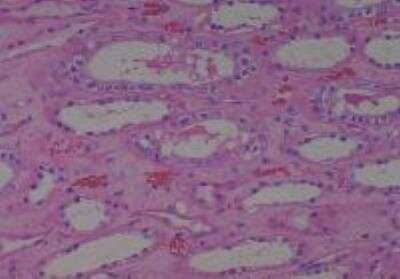

Scientific Data Images for Human Multi Tissue MicroArray (Normal Adjacent)

Hematoxylin & Eosin Stain: Human Common Tissue MicroArray (Normal Adjacent) [NBP2-30215] - 01. Stomach